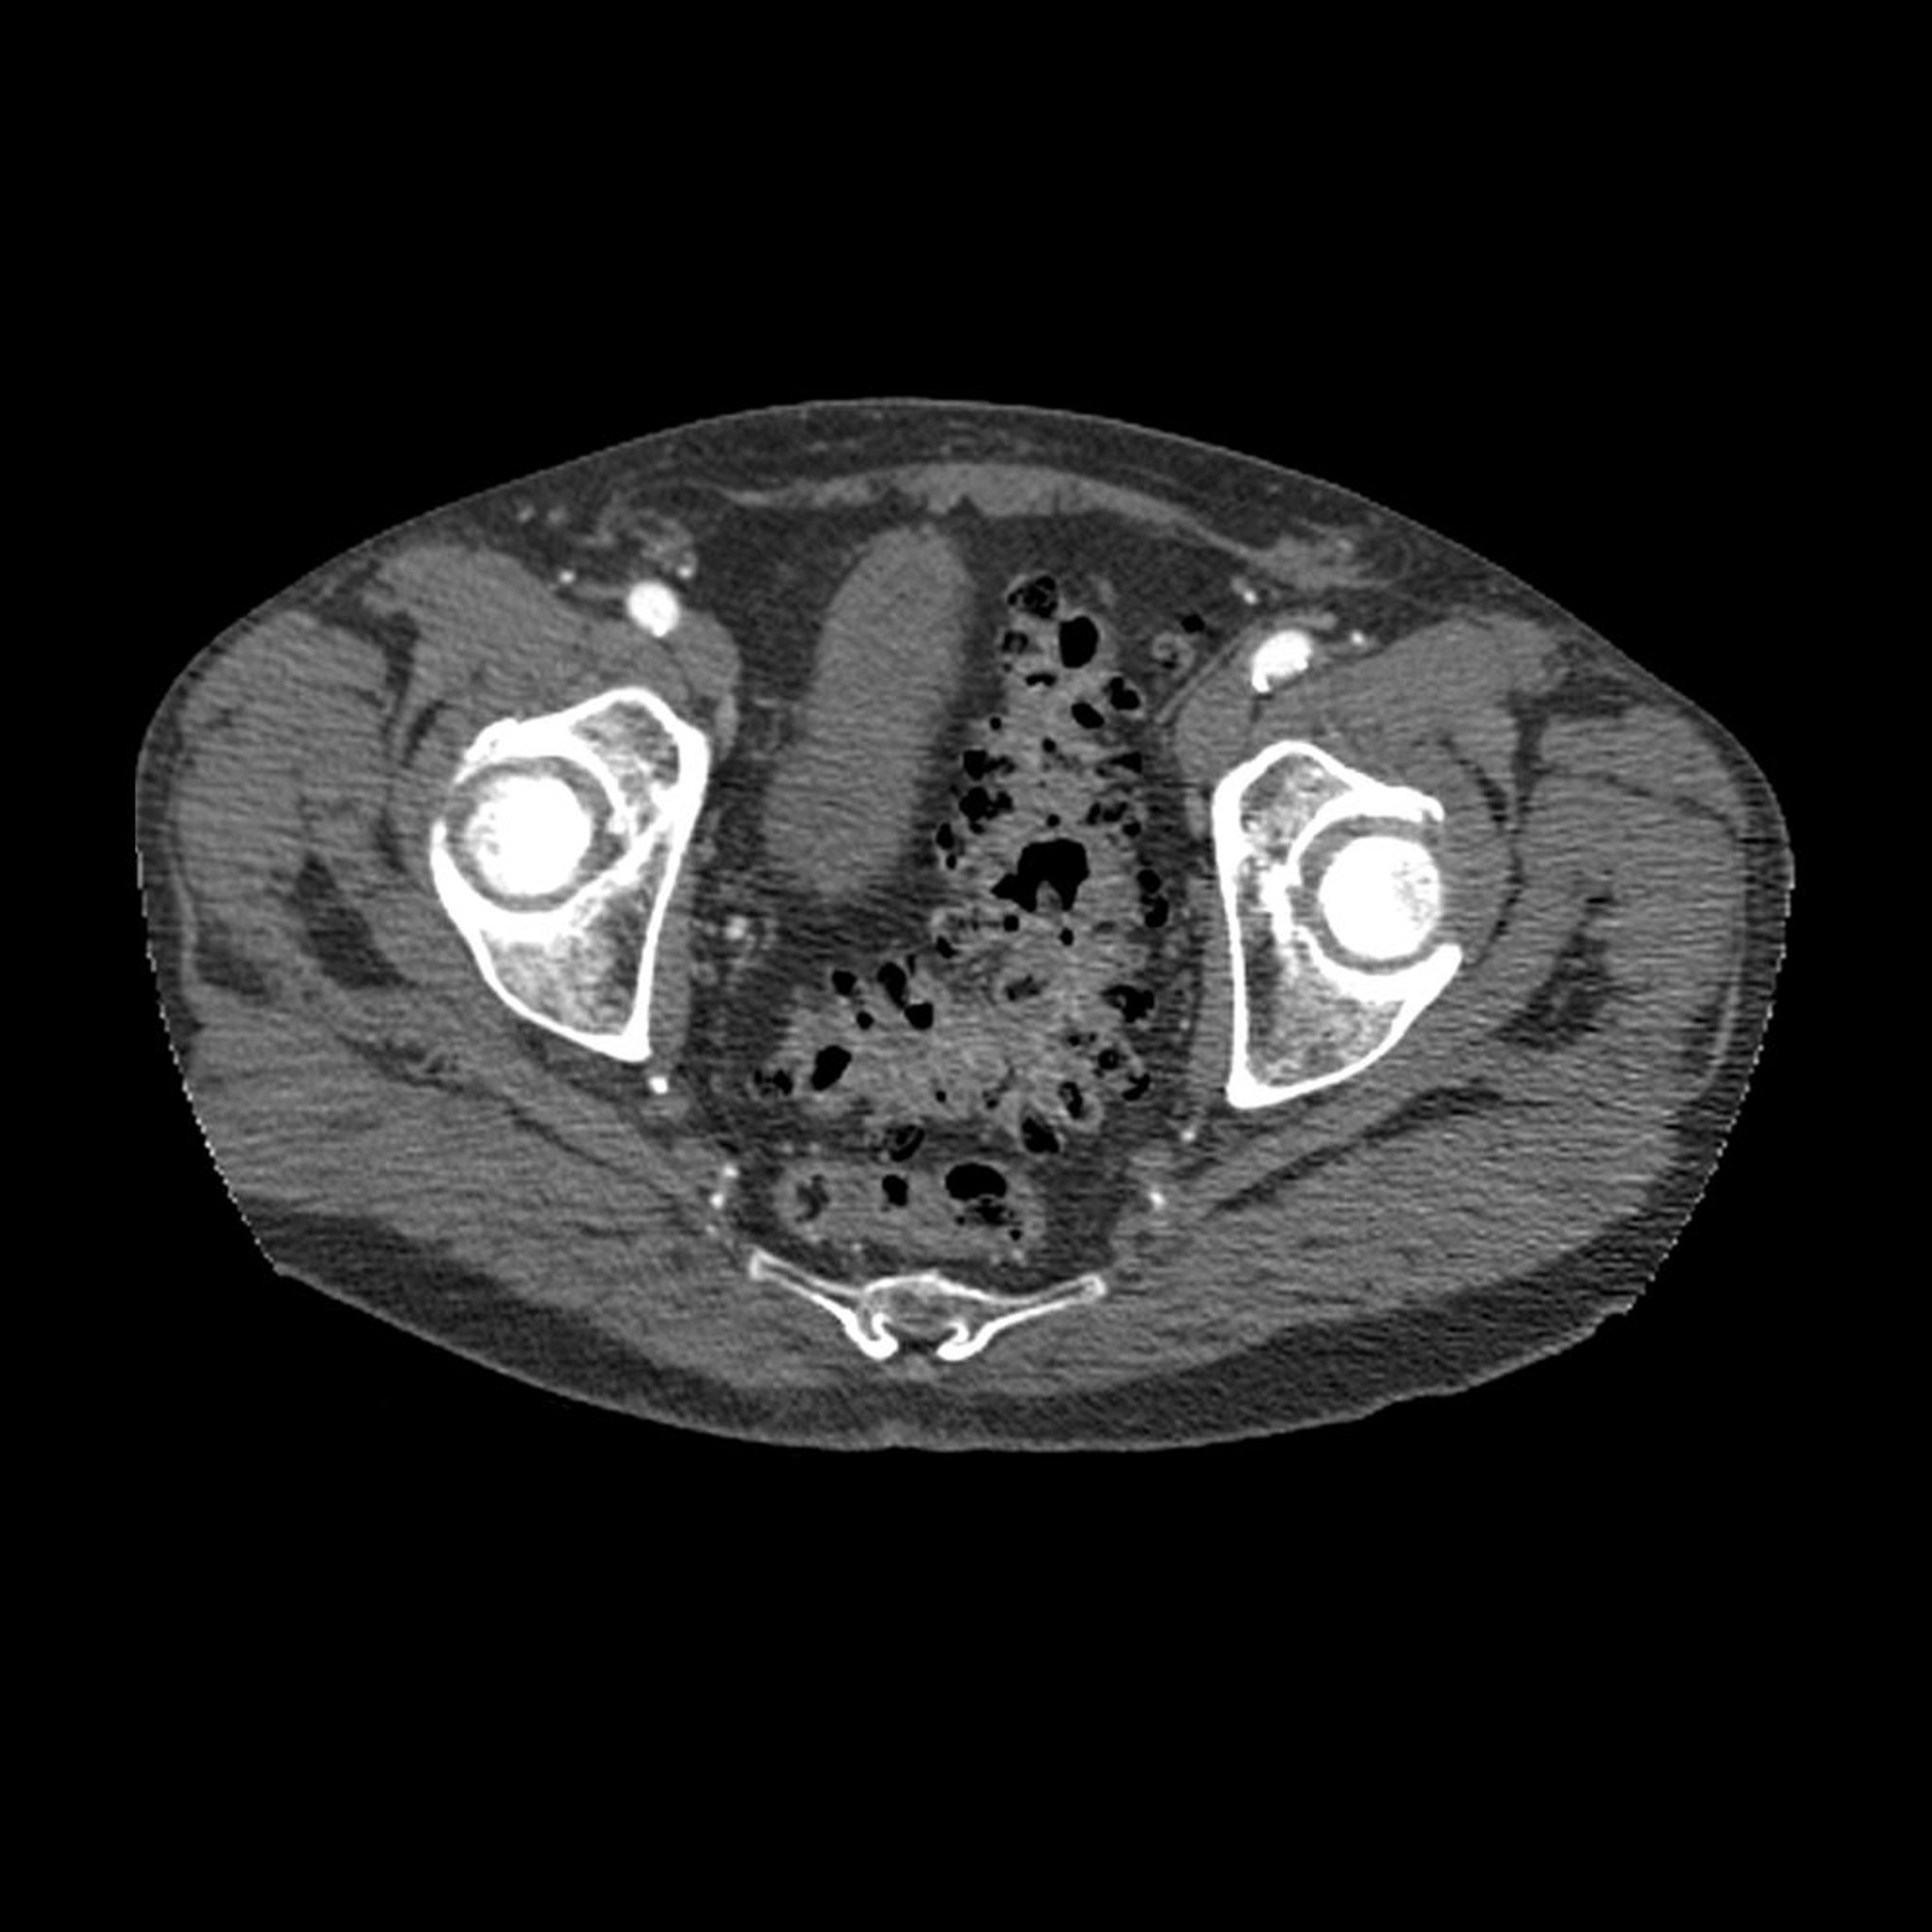

Este corte transversal de TC a través de la pelvis muestra el aspecto típico de la diverticulosis (las áreas oscuras en la pared del colon sigmoideo).